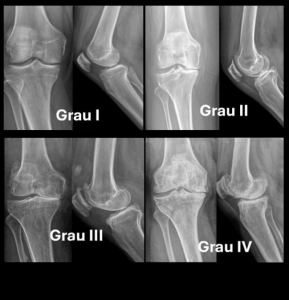

A pesquisa avaliou 224 pacientes atendidos no Into e indicou que a variação polimórfica GDF5 rs143384, do gene GDF5 (growth differentiation factor 5), está associada a quadros mais graves da osteoartrite, especialmente entre mulheres. Os resultados revelam que a frequência de uma variante genética desse gene polimórfico aumenta conforme a gravidade da doença.

Os dados mostram que, no geral, a idade mediana dos pacientes com osteoartrite de joelho é de 64 anos, com variação entre 44 e 84 anos. Além disso, aqueles com mais de 70 possuem formas mais avançadas da doença. A maior parte dos pacientes é do sexo feminino, com estatura inferior a 1,60 metro, e cerca de dois terços são obesos ou obesos mórbidos.